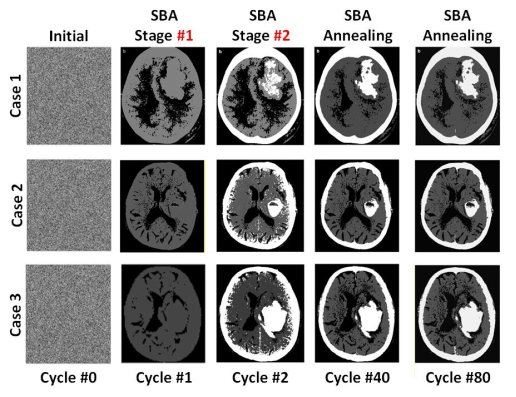

针对以上问题,bv伟德官方网站bevictor伟德官网陈卓俊教授团队成功设计并流片了一款多态组合优化问题专用处理器。提出了可重构波茨机架构,波茨单元耦合系数复用,以及逐次边界逼近退火技术,大幅提高了解决多态问题的面积效率以及能效。芯片采用65nm CMOS工艺制造,集成256个自旋单元,支持2~4bit的耦合系数位宽,兼容King’s Graph自旋网络拓扑结构,每个自旋的面积仅为4400μm2,并在CT图像聚类、合金相变模拟等应用中完成验证。与同期先进工作相比,该处理器在求解速度、归一化面积等方面达到了最优水平。